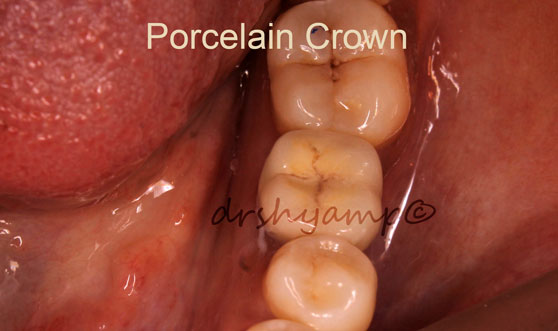

single molar dental implant

single molar dental implant

single molar dental implant

single molar dental implant

single molar dental implant

single molar dental implant

single molar dental implant

single molar dental implant

single molar dental implant

single molar dental implant

single molar dental implant

single molar dental implant

single molar dental implant

single molar dental implant

single molar dental implant